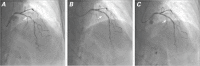

Coronary artery disease of the septal perforator branches can lead to clinical ischemia and conduction abnormalities. Performing interventional procedures in these vessels is frequently impossible because they are small, which makes it difficult to approach them and to select appropriate equipment. Larger septal perforator branches have been treated percutaneously in a few patients; however, the clinical effectiveness and long-term outcomes are not known. We present our experience in managing obstructive septal perforator branch stenosis in 4 patients.